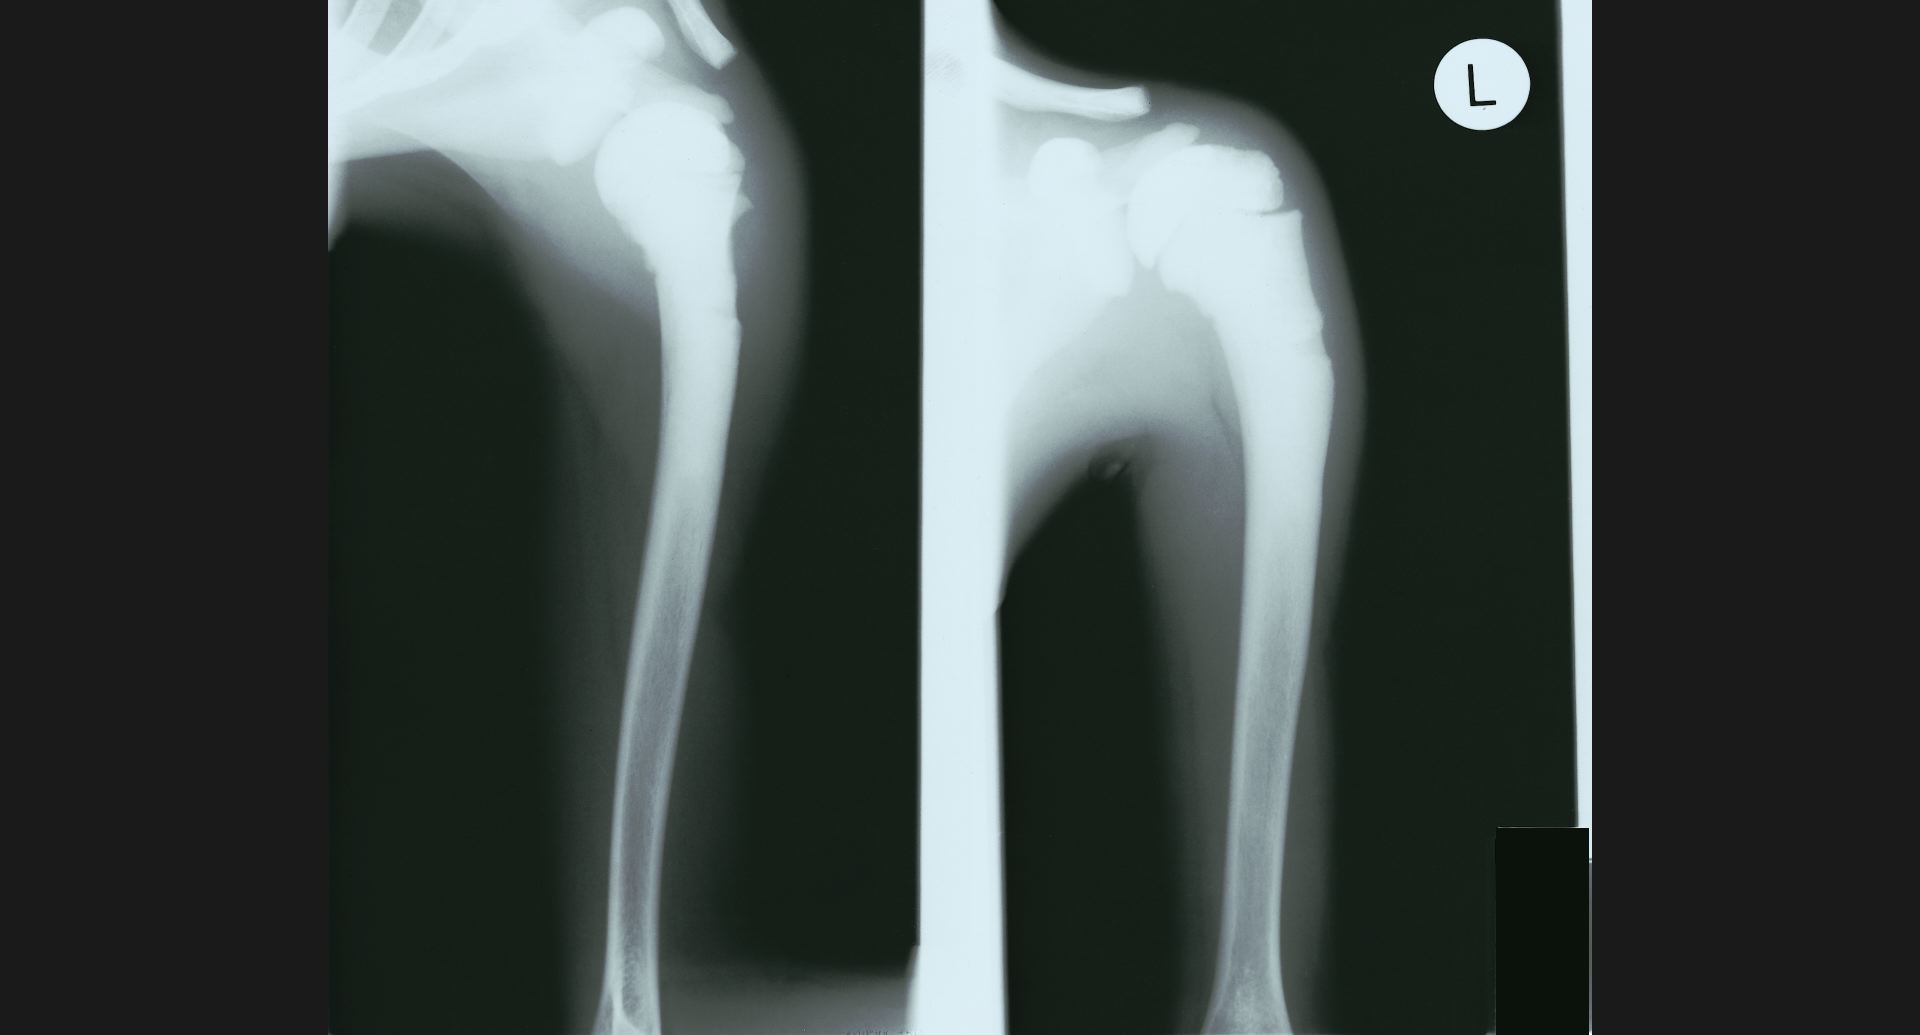

:Fibrous dysplasia骨頭のtrabeculation。病変部。

fig.16(93KB)